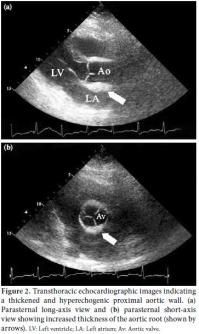

A 48-year-old female patient with no known cardiovascular risk factors was referred to our emergency department due to the sudden onset of severe, constricting chest pain that had been occurring for the previous four hours. On physical examination, blood pressure measurements from the right and left arms were 155/90 and 130/80 mmHg, respectively, and an apical 2/6 systolic heart murmur was heard. Electrocardiography (ECG) showed a 1 mm ST-segment depression in the precordial derivation and a 1.5 mm ST elevation in augmented vector right (aVR) (Figure 1). Laboratory tests revealed a creatinine level of 1.8 mg/dL, a urea level of 80 mg/dL, and slightly increased troponin/creatine kinase-MB fraction (CKMB) levels. Based on the patient's medical history, she had been diagnosed with Takayasu's arteritis 12 years earlier due to renal artery stenosis, subclavian artery stenosis, and intermittent claudication. In addition, a pulmonary embolism had been detected four years previously. Transthoracic echocardiography showed normal left ventricular systolic function, mild aortic regurgitation, and moderate tricuspid regurgitation. The systolic pulmonary artery pressure was 35 mmHg. The ascending aorta was measured as 4.0 cm, and no dissection flap was detected. An echocardiographic examination revealed that the proximal aorta was thickened and hyperechogenic, and calcific plaques were commonly observed on the inner surface of the lumen (Figure 2). Using suprasternal imaging, it was determined that the arcus aorta was 4.3 cm in width, and moderate proximal brachiocephalic, common carotid, and subclavian artery stenoses were detected. Thickening of the arcus aorta wall was observed in addition to an increased echogenic area and a rough inner lumen (Figure 3). Due to ongoing severe chest pain, the patient was urgently transferred to the catheter laboratory. Spontaneous dissection causing severe stenosis in the proximal left main coronary artery (LMCA) was detected by coronary angiography (Figure 4), but all other coronary vessels were normal. In addition, there was no significant narrowing observed on the carotid Doppler ultrasound. The patient's hemodynamic values were normal, and an emergency operation was planned. Ascending aorta, upper, and lower vena cava cannulations were performed after a median sternotomy and then the patient entered into the pump. The heart was stopped by cold potassium while the patient was under general (rectal temperature 28 °C) and topical hypothermia. During an intraoperative evaluation of the thoracic aorta, it was noted that it was completely calcified and hardened. Aortocoronary anastomosis was performed using a saphenous venous graft because of the ostial involvement of the subclavian and left internal mammary arteries (LIMA). The postoperative course was uneventful, and the patient was discharged on postoperative day 10.

Takayasu's arteritis, also known as Martorell's syndrome, is an inflammatory disease that often affects the aorta and the proximal segments of the main aortic. It also may result in vascular occlusion due to intimal fibrosis and thickening. In addition to ostial stenosis, aorta aneurysms may be encountered, depending on the existence panarteritis. This is especially true if there is destruction of the tunica media. The cause of Takayasu's arteritis is not yet known, but it is more common in young females. Symptoms vary depending on the involvement and severity of the functional impairment of the organs supplied by the stenotic vessels. During the early stage, rheumatic complaints such as fever, malaise, fatigue, general body pain, and weight loss may occur due to the systemic inflammatory condition. As a result of chronic vascular inflammation, intimal fibrosis may result in catastrophic outcomes, such as organ ischemia. Arm and leg pain, renovascular hypertension, and neurological symptoms may develop in patients during advanced stages of this disease. Pulmonary arterial hypertension and emboli are also often observed due to the involvement of the pulmonary artery. A diagnosis of Takayasu's arteritis is made clinically according to the presence of at least three of the American College of Rheumatology (ACR) 1990 criteria:[2] (i) disease onset prior to age 40, (ii) claudication of the extremities, (iii) reduction in the brachial pulse, (iv) more than a 10 mmHg pressure difference between the two arms, (v) detection of a murmur around the aorta, subclavian artery, or both, and (vi) abnormal arterial imaging. There are no specific blood tests for Takayasu's arteritis. Medical treatments include immunosuppressive therapy, such as steroids, cyclophosphamide, and methotrexate, but there is no current agreement on the best treatment option. Coronary artery involvement occurs in 5-15% of patients. Although Takayasu's arteritis often causes ostial stenosis, spontaneous LMCA dissection is an extremely rare complication.[3] In the case of sudden-onset chest pain in a patient with this disease, coronary artery dissection should be considered due to the need for early diagnosis and rapid treatment. However, dissection of the ascending aorta should be excluded. In our patient, transthoracic echocardiography (suprasternal view) did not show aortic dissection. Therefore, computed tomography (CT) and magnetic resonance imaging (MRI) were not performed because of poor renal function. An echocardiographic examination should be used during routine follow-up of all patients with Takayasu's arteritis to evaluate aortic involvement. Transthoracic echocardiography is non-invasive and inexpensive and has been proven to be an excellent method for patient diagnosis and follow-up. Intimal thickening and hyperechogenic appearance due to calcification of the aorta and its major branches are important and valuable observations. As in our patient, echocardiography may be useful as an alternative to MRI and CT for detecting ostial stenosis of the main branches. Percutaneous coronary intervention (PCI) for left main coronary stenosis has been described in the literature; however, invasive treatments should be decided upon according to the lesion location, number of stenotic vessels, and available technical equipment.[4] There are currently no clinical studies showing the superiority of percutaneous intervention over surgical therapy in patients with Takayasu's arteritis complicated by left main coronary dissection. Due to the risk of entering a false lumen, surgical management was planned. In our patient, an internal mammary artery (IMA) graft was not used because there were advanced fibrotic changes and calcification in the aorta and its major branches. A saphenous graft was preferred, as previous reports have shown lesser venous involvement with this procedure.[5] A careful preoperative echocardiographic examination with suprasternal views is suggested, which can provide the surgeon with adequate information regarding graft choice. When intimal thickening is intense and subclavian ostial stenosis is detected, saphenous graft selection should be given priority. No guidelines are currently available regarding percutaneous intervention to protect the LMCA following surgery for its dissection in patients with Takayasuʹs arteritis.